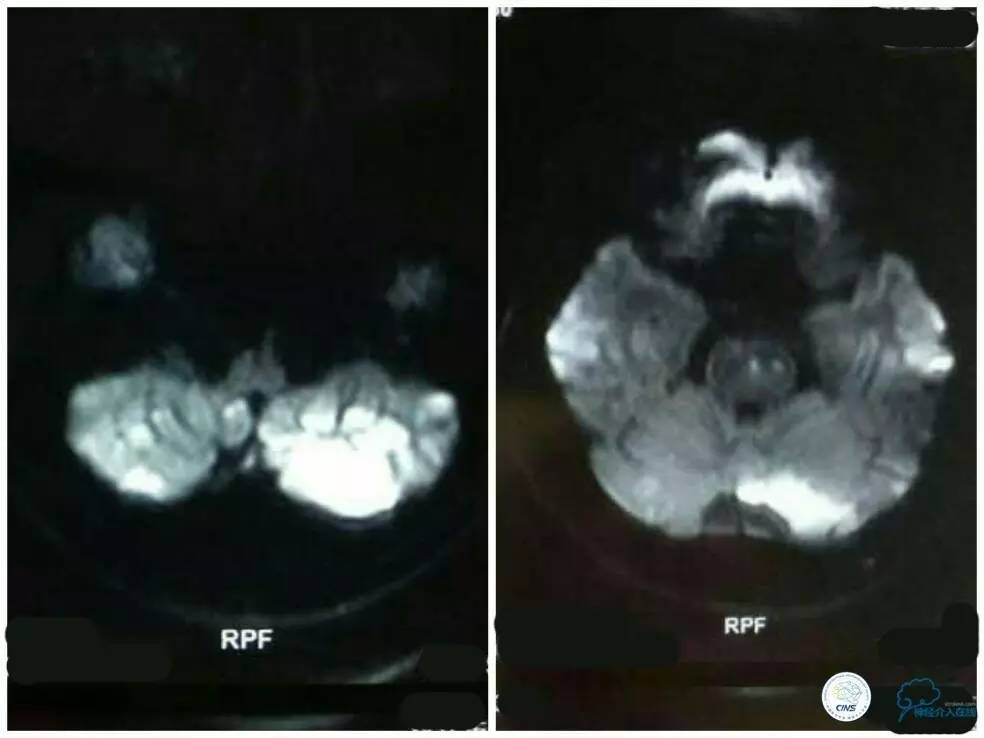

2个月前当地医院行MRI检查提示:双侧小脑半球及桥脑多发新近脑梗死(图1)。

图1